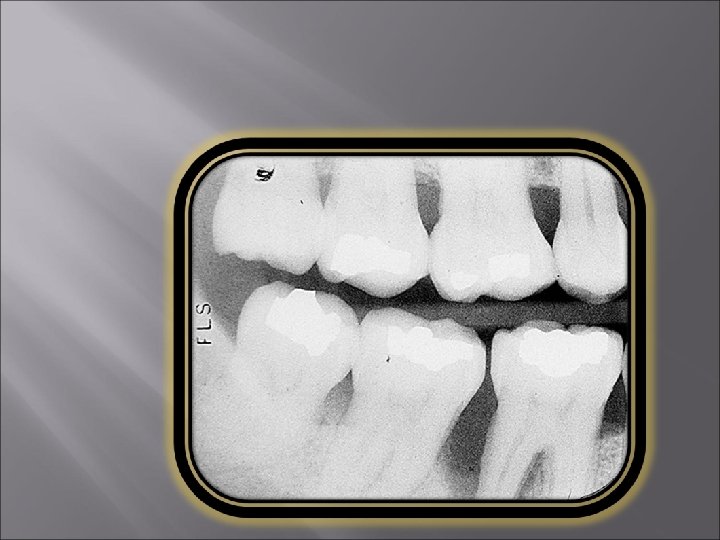

Moderate to severe Periodontitis